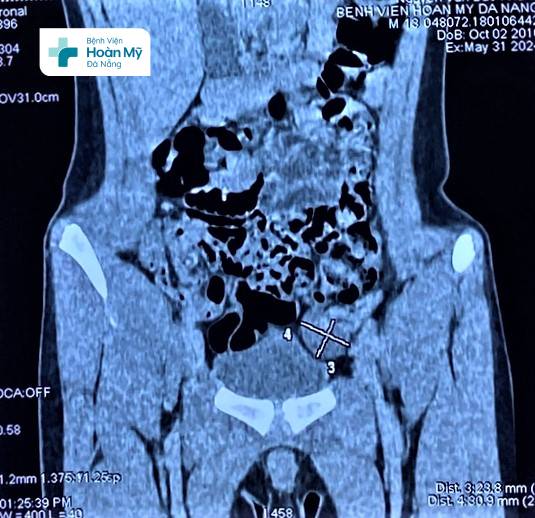

“Khi tiếp nhận, chúng tôi tiến hành thăm khám, xác định chỉ có tinh hoàn phải ở trong bìu, còn tinh hoàn trái không có ở bìu, và khám không thấy ở ống bẹn trái. Do đó trẻ được chỉ định siêu âm, chụp cắt lớp vi tính để tìm kiếm chính xác vị trí của tinh hoàn trái. Kết quả cận lâm sàng cho thấy tinh hoàn trái của trẻ nằm lạc chỗ trong ổ bụng. Với tình trạng này bé cần được can thiệp phẫu thuật sớm để đưa tinh hoàn về đúng vị trí ” – BS. Bùi Quốc Triệu – Trưởng khoa Ngoại Tiết Niệu – Nam khoa, BV Hoàn Mỹ Đà Nẵng cho biết.